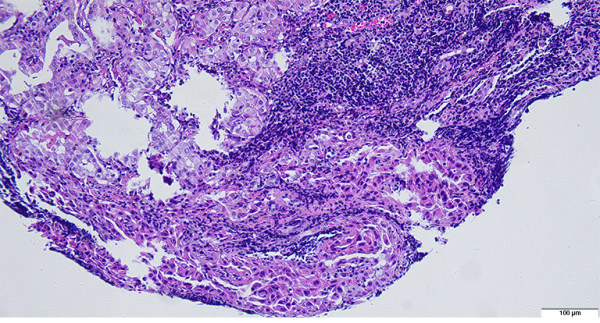

Histologic evaluation of sentinel and non-sentinel axillary lymph nodes in breast cancer by multilevel sectioning and predictors of non-sentinel metastasis

Piyarat Jeeravongpanich, Tuenjai Chuangsuwanich, Chulaluk Komoltri, Adune Ratanawichitrasin